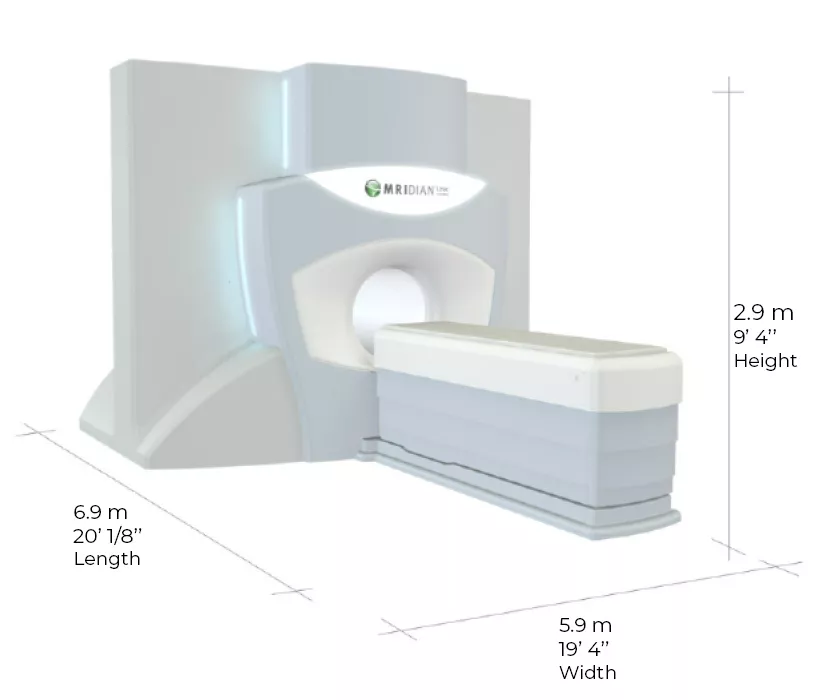

YER VE ZAMANDAN TASARRUF

MRIdian’ın SmartSITE tasarımı, neredeyse tüm mevcut standart LINAC kasası ve ekranlama konfigürasyonlarına uymasını sağlayarak uzun kurulum programlarından ve özel, büyük ölçekli kasalar oluşturmak için gereken ek maliyetlerden kurtarır. MRIdian bileşenleri ayrıca geleneksel kasa kapılarına da sığabilir, bu nedenle duvarları kaldırmaya, tavanları yükseltmeye veya etrafını kazmaya gerek kalmadan kesintileri ve gecikmeleri ortadan kaldırır.